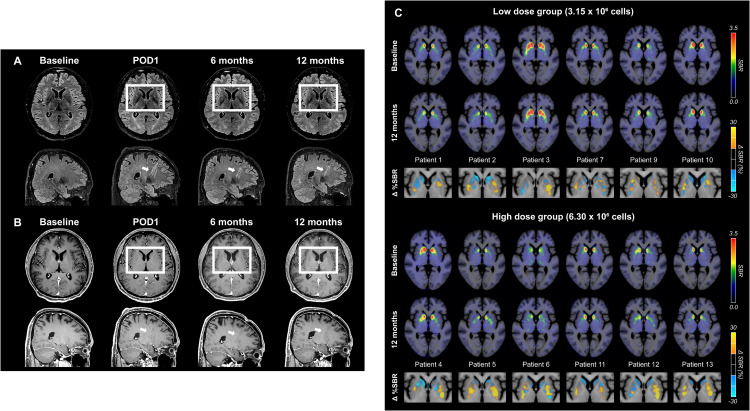

術(shù)后MRI顯示,移植區(qū)域未出現(xiàn)腫瘤或明顯炎癥反應(yīng),細(xì)胞被準(zhǔn)確植入殼核目標(biāo)區(qū)域,初步證明手術(shù)和細(xì)胞定位的安全性與可控性。

更關(guān)鍵的證據(jù)來自多巴胺轉(zhuǎn)運(yùn)體PET成像。與基線相比,后背側(cè)殼核區(qū)域的DAT信號在高劑量組明顯升高,且這種變化與患者停藥狀態(tài)下的運(yùn)動改善程度呈顯著相關(guān)。這意味著,影像學(xué)上觀察到的多巴胺能功能增強(qiáng),與臨床癥狀的改善方向一致。(圖6)

這些結(jié)果共同表明:移植的多巴胺祖細(xì)胞不僅在腦內(nèi)存活,而且在關(guān)鍵運(yùn)動環(huán)路中實(shí)現(xiàn)了功能性整合,并與實(shí)際運(yùn)動改善相對應(yīng)。